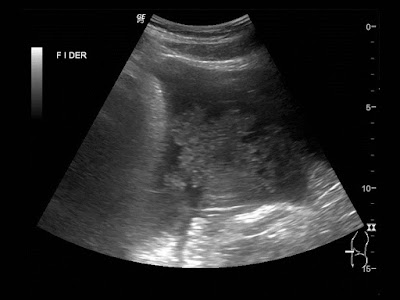

Paciente de 12 años con dolor abdominal. Remitida para estudio de masa intraabdominal.